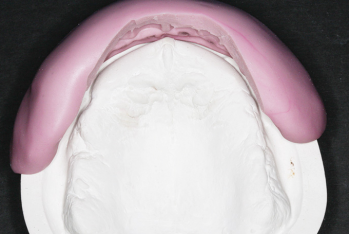

Article réservé à nos abonnés Prothèse amovible complète unimaxillaire : un traitement souvent complexe

Sans conteste, il s’agit du traitement prothétique le plus compliqué à résoudre pour le praticien.En effet, il convient de gérer...